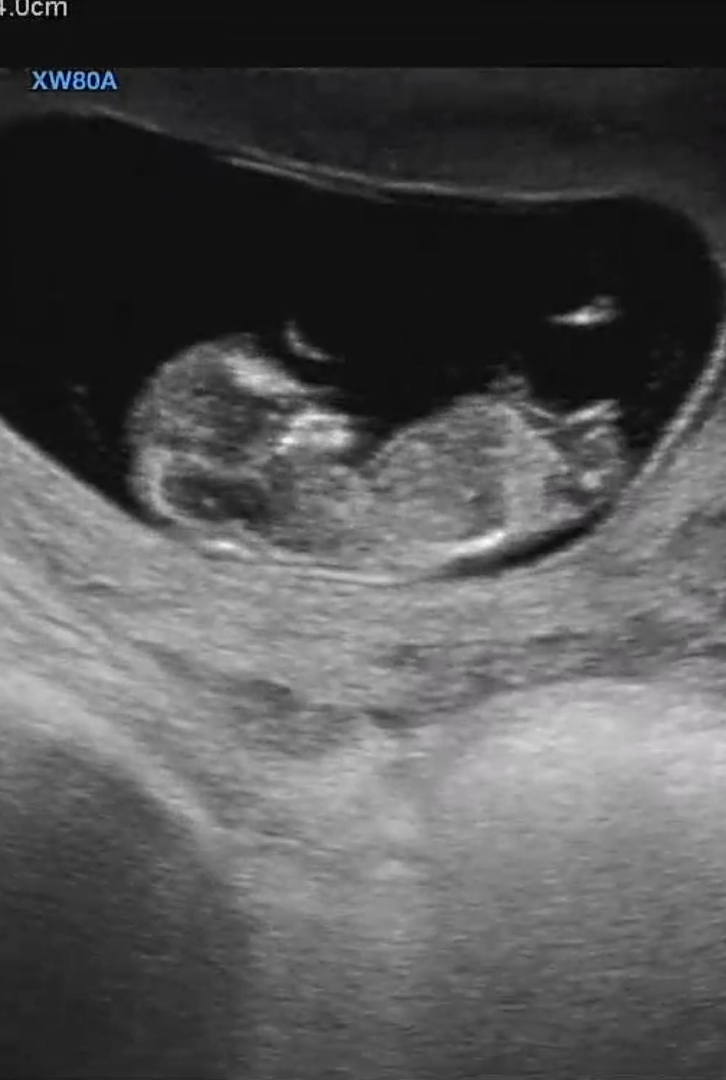

11주 각도법..?

오늘 11주 2일인데 이게 탯줄인지 생식기인지 헷갈리기도 하고 각도법 보자니 좀 이른 것 같아서 다른분들의 의견을 듣고싶어요!

딸 같아요ㅎㅎ